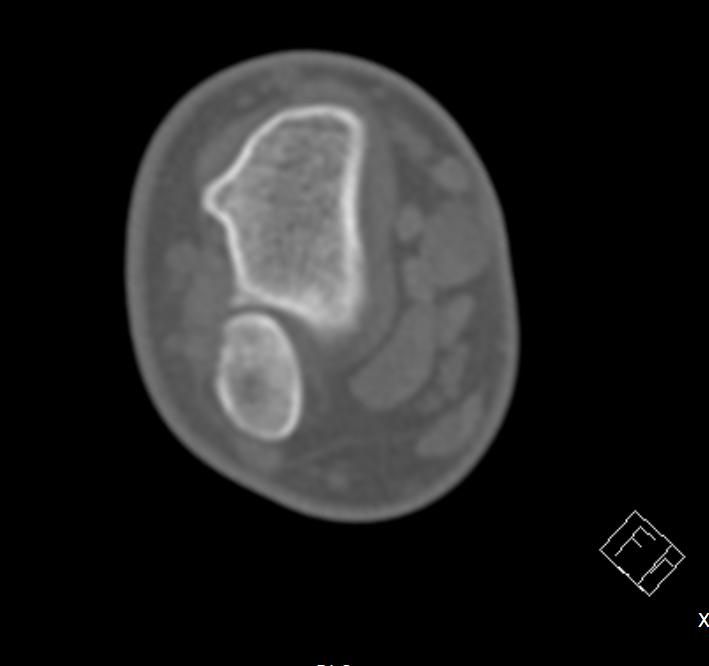

10년전 왼팔의 두 뼈가 골절됨과 동시에 휘어져서 응급실에서 뼈를 돌려서 맞추고 깁스를 했는데 그 이후로 왼쪽으로 팔이 회전하지 않습니다 ct 사진도 첨부해드리겠습니다

사진상 "요.척골이 회전 변형된 채로 붙은 부정유합" 가능성이 커 보입니다.

이 경우 팔꿈치.전완 "회전 제한(회내/회외 장애)"이 오래 지속될 수 있습니다.

올려주신 사진과 증상을 참고했을 때, 팔꿈치 관절을 구성하는 요골과 척골의 정렬이 크게 뒤틀려져 보이지는 않지만 골절 유합시 미세한 각 변형이나 척골과 요골 사이 인대와 같은 연부조직의 유착 또는 요골과 척골의 관절의 기능이상등으로 인해 나타나는 증상으로 생각됩니다.